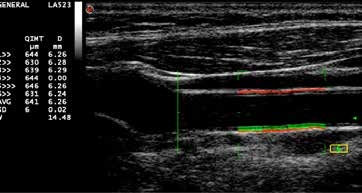

3. QIMT i QAS – Vaskularni biomarkeri u predviđanju rizika

Kod pacijenata sa povišenim kardiovaskularnim rizikom (hipertenzija, dijabetes, dislipidemija, pozitivna porodična anamneza), kardiolog ne procenjuje samo srčanu funkciju, već i stanje krvnih sudova. Tu QIMT i QAS na MyLab X8 daju dodatne informacije, bez potrebe za zasebnom opremom.

MyLab X8 koristi radiofrekventnu (RF) tehnologiju vaskularnog ultrazvuka, koja stoji iza alata:

QIMT (Quality Intima-Media Thickness) – kvantitativno merenje debljine intima–medija sloja karotidne arterije,

QAS (Quality Arterial Stiffness) – analiza lokalne arterijske krutosti i brzine širenja pulsnog talasa (pulse wave velocity – PWV).

Za razliku od klasičnih merenja, RF pristup koristi „sirov“ ultrazvučni signal visoke rezolucije, što omogućava preciznije merenje promena - veličine već od nekoliko mikrometara. Sistem u realnom vremenu daje povratnu informaciju o kvalitetu merenja (prosek i standardna devijacija kroz više srčanih ciklusa), što dodatno povećava pouzdanost nalaza.

Šta to znači u svakodnevnoj praksi:

standardizovana merenja debljine karotidne intime–medije, sa visokom prostornom rezolucijom i povratnom informacijom o kvalitetu u realnom vremenu,

procena lokalne elastičnosti / krutosti zida arterije (lokalna distenzija, lokalni pulsni pritisak, lokalni PWV i indeksi krutosti), na nivou karotidne ili femoralne arterije;

mogućnost da se prati efekat terapije (npr. statini, antihipertenzivi, promene načina života) kroz vreme, ne samo preko laboratorije i kliničke slike, već i preko objektivnih vaskularnih biomarkera;

bolje razlikovanje pacijenata u „sivoj zoni“ rizika (npr. srednji SCORE/Framingham) – gde dodatna informacija o debljini intima–medija sloja i lokalnoj krutosti može da „prelomi“ odluku o intenzitetu preventivne terapije;

sve to na istom aparatu na kom radite standardni ehokardiogram i dopler krvnih sudova, u okviru jednog pregleda, bez komplikovanja organizacije rada.

QIMT i QAS tako praktično integrišu strukturalni (IMT, plak) i funkcionalni (krutost, PWV) aspekt krvnih sudova u svakodnevni rad kardiologa, što olakšava realnu, individualizovanu procenu kardiovaskularnog rizika za svakog pacijenta.